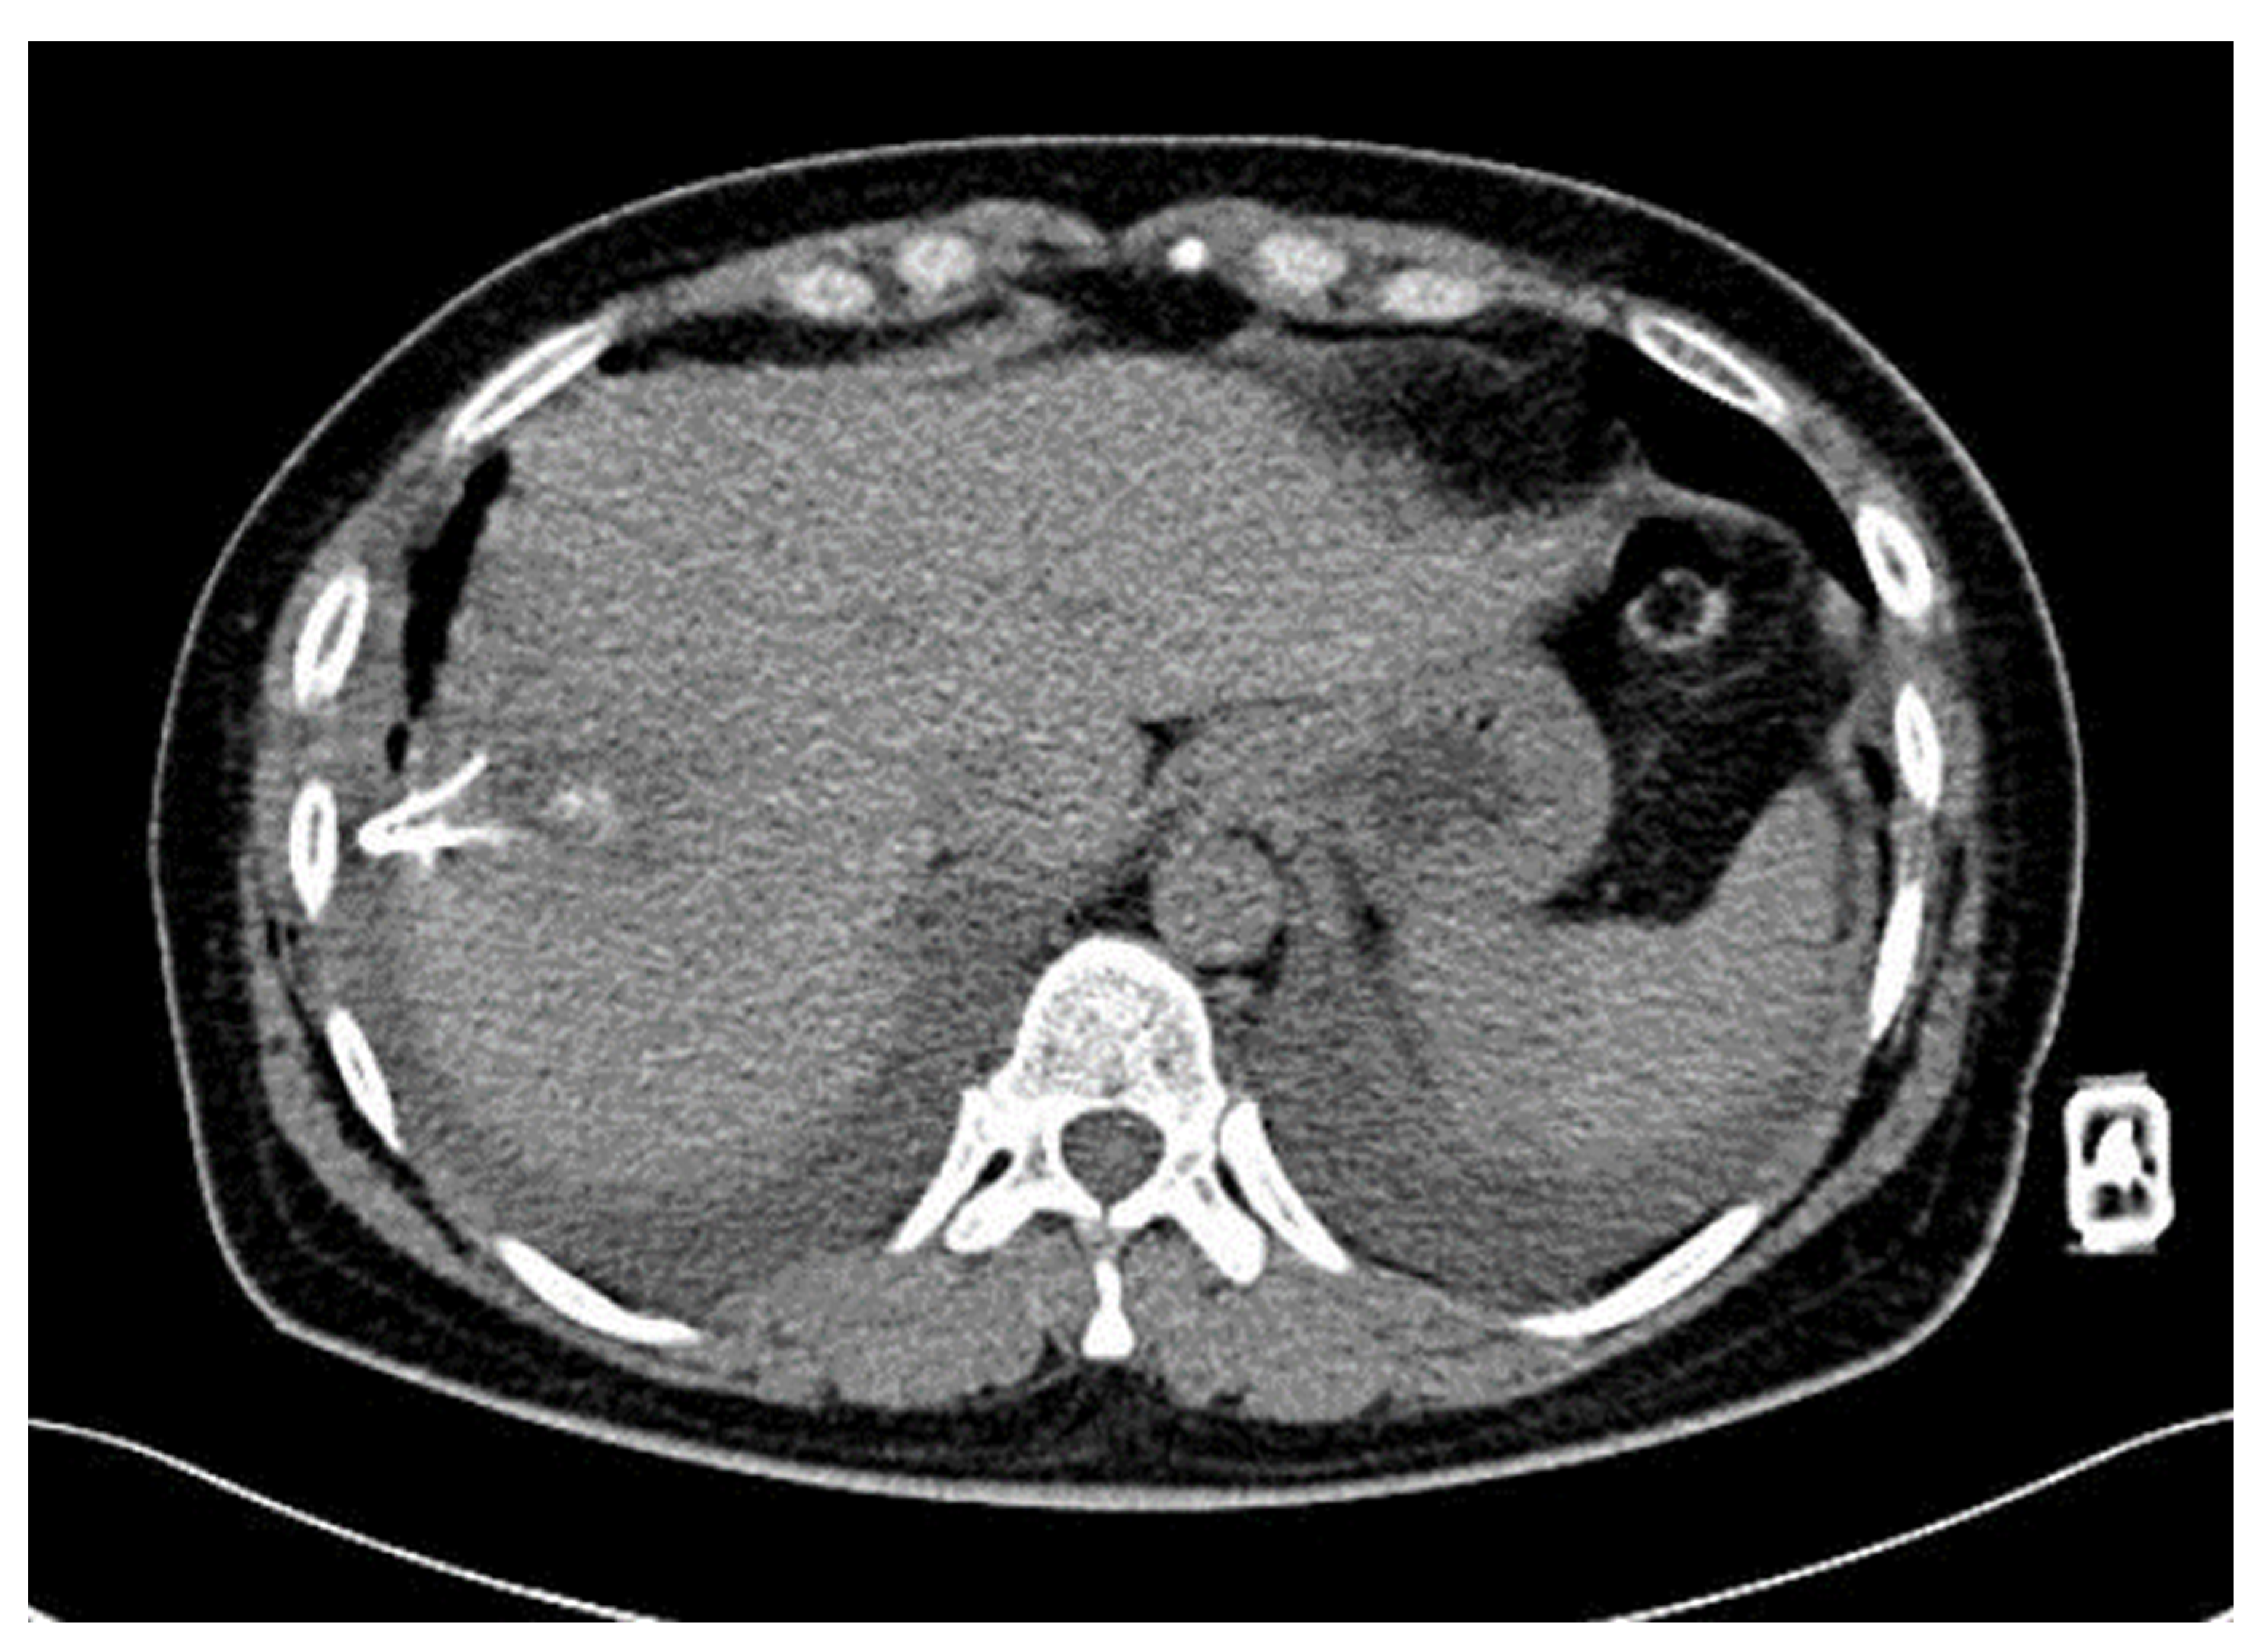

Diaphragmatic Liver Herniation after Radiofrequency Ablation of a Secondary Liver Tumor